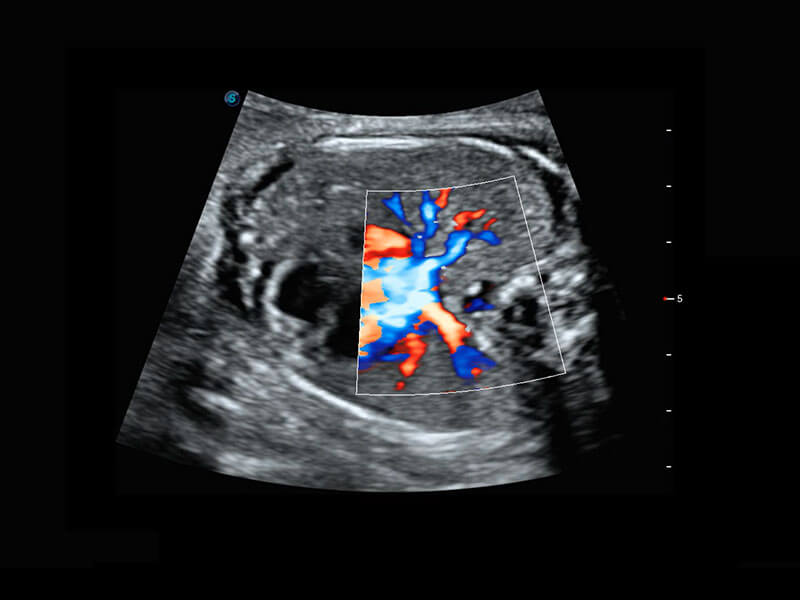

乳腺超声 / 新生儿

P60搭载宽频带线阵探头、宽景成像、弹性成像技术,为您提供乳腺应用方案。P60支持高频相控阵探头、线阵探头、腹部高频探头、腹部微凸探头等,丰富的探头群搭载敏感的彩色血流成像,适用于新生儿多种脏器检测要求,满足新生儿筛查需求。

• 新生儿心脏